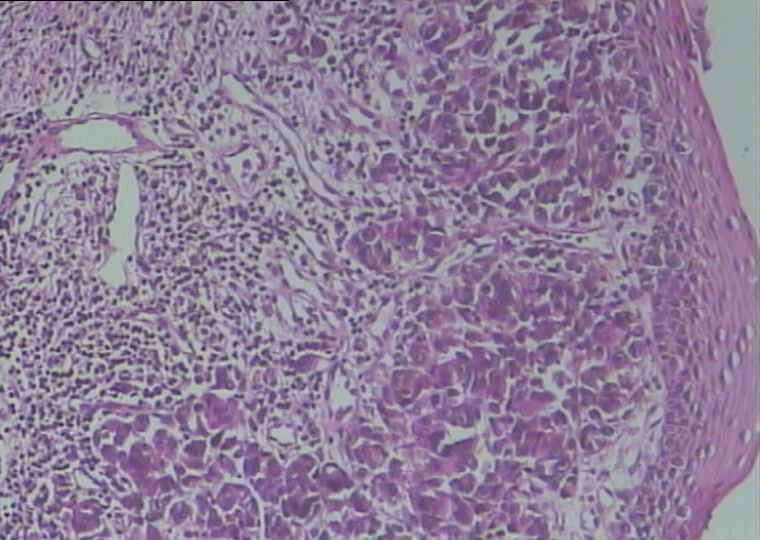

鼻咽肿物

倾向恶黑,也需要排一下横纹肌肉瘤,看看大家意见